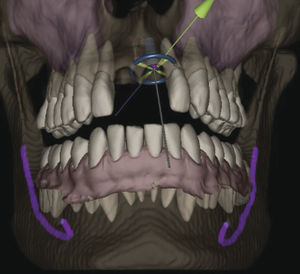

... Xelis Dental es un avanzado software de reconstrucción 3D que puede utilizarse de forma independiente o con INFINITT Dental PACS, y que ofrece mediciones precisas e información anatómica sobre estructuras orales ...

... implantes Además de una biblioteca llena de recursos, puede añadir cualquier accesorio nuevo importando el archivo STL en el software. Crear alineador de carcasas Crear alineadores de carcasas acorta automáticamente ...